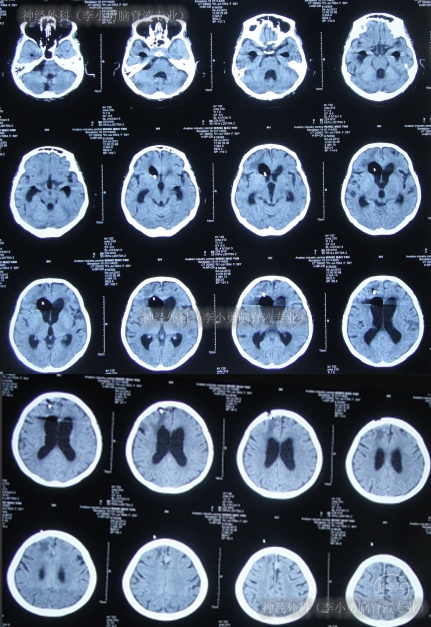

2013年1月9日(李小勇脑脊液专业治210天)出院,出院时:由入院时病危、昏迷,鼻饲、插尿管变得神志清楚、肢体遵命活动基本正常,饮食正常,大小便正常,仅腿部力量差些不能自己走路(图-22)。出院时头颅CT示无异常(图-23)。

图-23:出院时头颅CT

出院后4月余即2013年5月13日,来院复查:腿部力量有所增加,在搀扶下能走路;查头颅CT示无异常(图-24)。